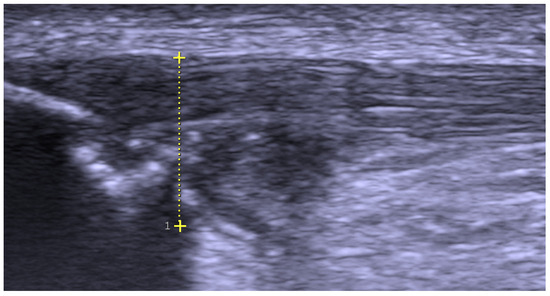

2.2. Pre-Operative Examination